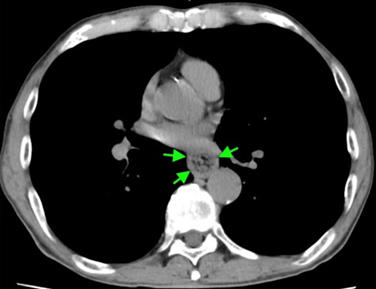

そこで胸部CTを確認したところ,食道壁の肥厚および食道内腔の腫瘤影(実は食物の塊)を認めます1。

この症例は特徴的な病歴と胸部CTから,『ステーキハウス症候群(steakhouse syndrome)』と診断しました。

ステーキハウス症候群は、食物の塊による食道閉塞であり、食物を飲み込んだ直後に発症するのが特徴です1。食物による消化管閉塞の呼称としては,food bolus impactionがより一般的ですが,印象的な名前の症候群であり今回取り上げてみました。高齢者(通常60歳以上)に生じることが多く,充分咀嚼されていない肉の塊を飲み込んだ後に発症することが多いことから,「ステーキハウス」症候群と呼ばれますが2,肉以外の食物も原因になり得ます。今回は「カツオのたたき」症候群ですね!

腫瘤のようなCT所見から,食道癌などと誤認される可能性がありますが,ステーキハウス症候群の場合は,突然発症ですので,腫瘤による嚥下障害とは異なった病歴になるはずです。